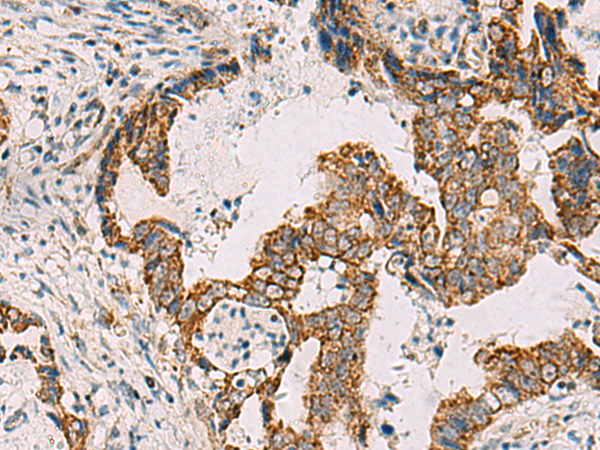

IHC positive control: |

Human cervical cancer and Human tonsil |

IHC Recommend dilution: |

50-300 |